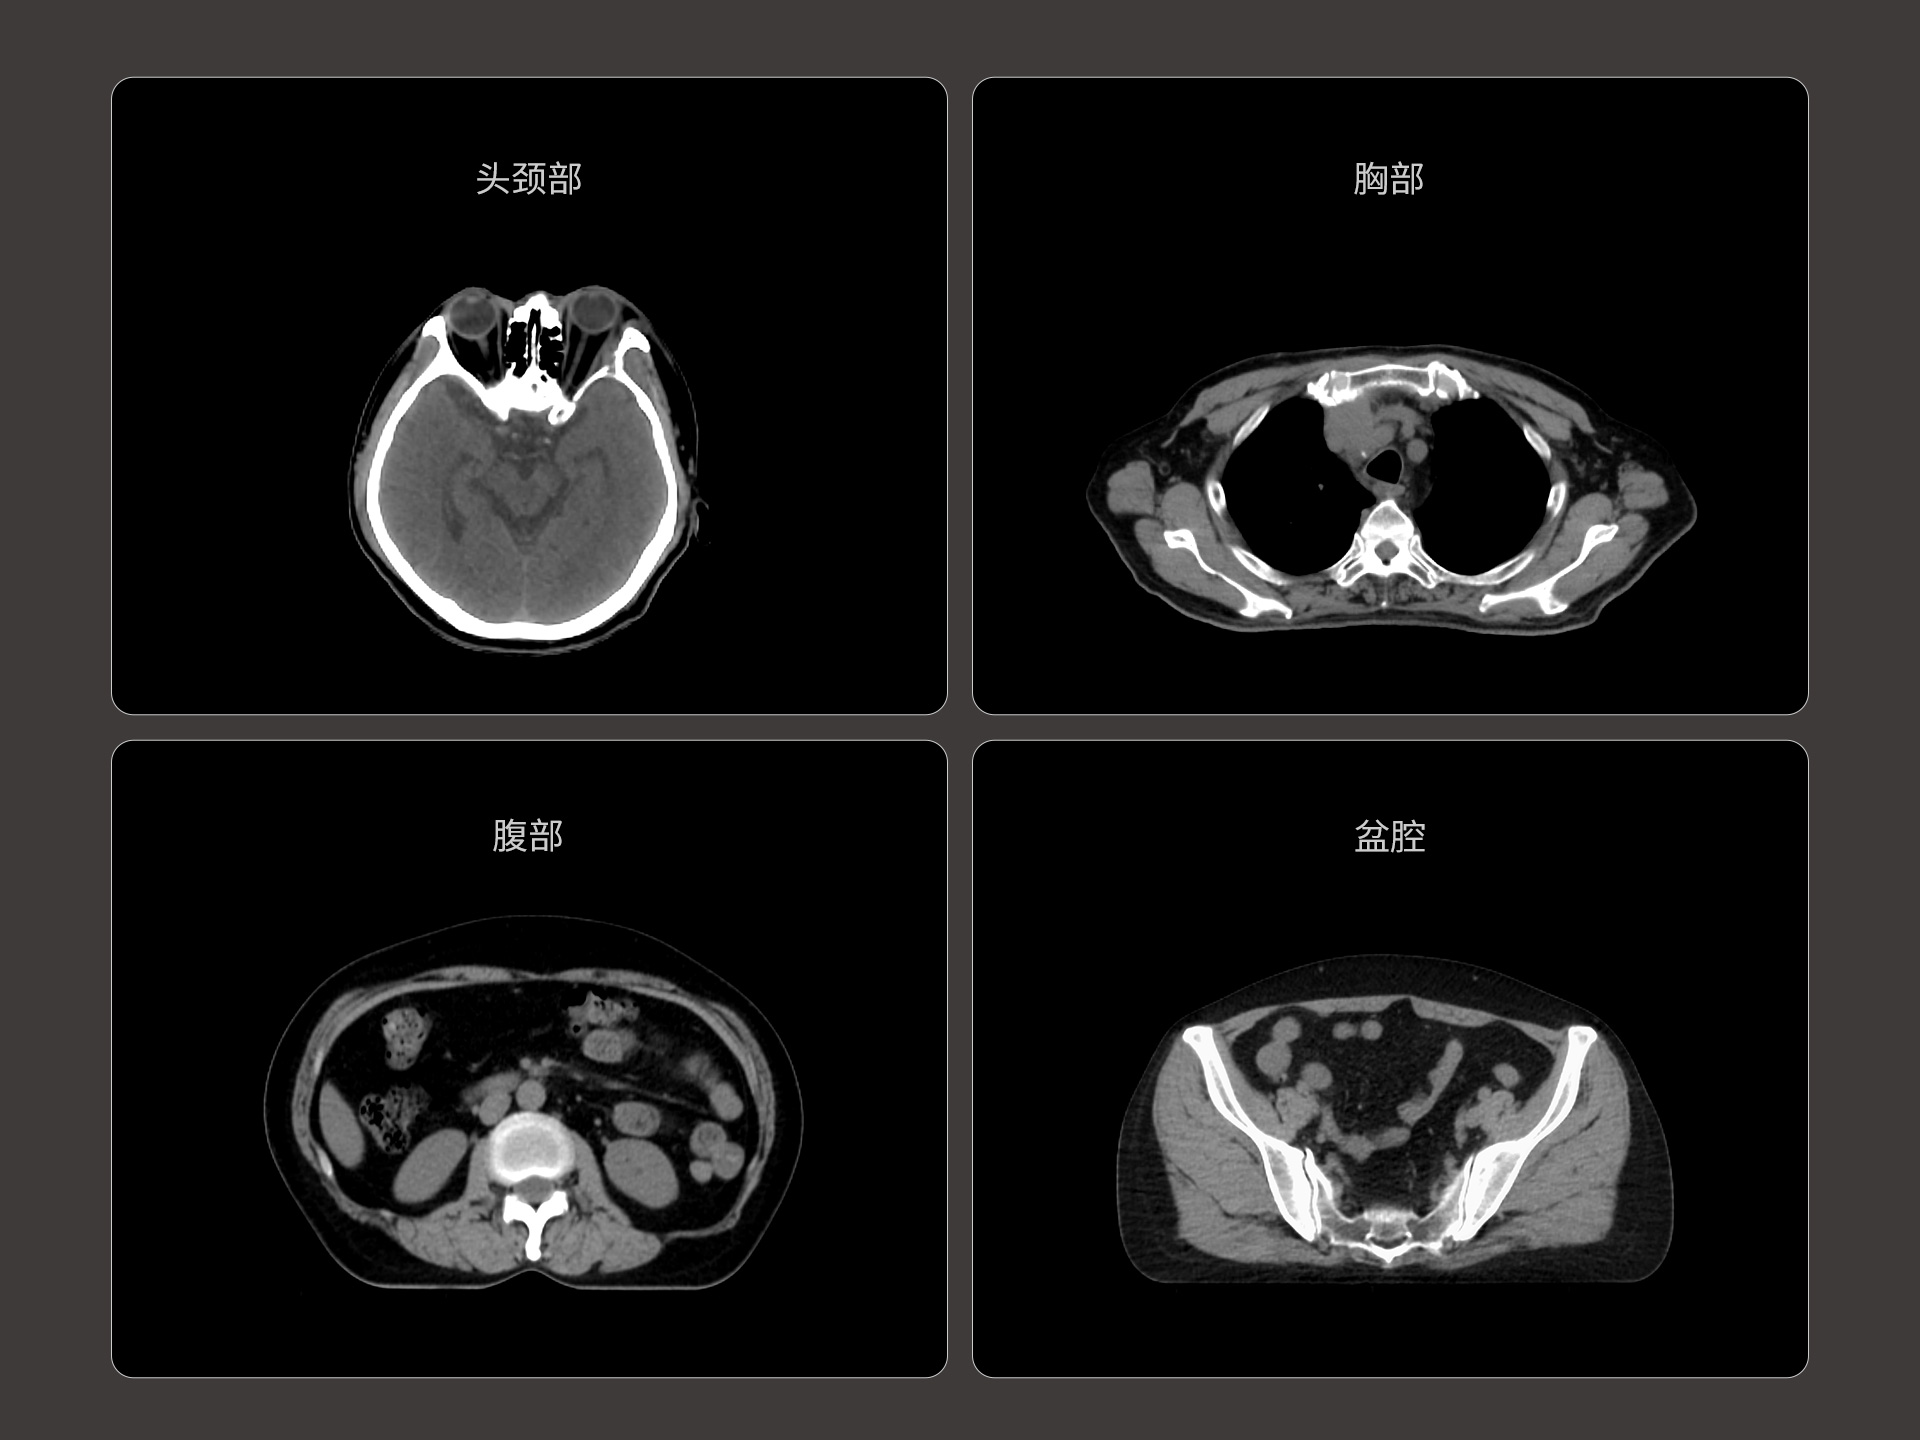

uLinac HalosTx®搭载新一代 87cm 大孔径诊断级CT图像引导系统,全能进阶,实现高清图像质量和全景视野的完美平衡,开辟全疗程 「影像感知」 ,为临床提供更自信、更全面的临床依据。

全疗程肿瘤变化感知,加速高清影像引导高水平普及

87cm CT影像孔径设计适配多种摆位姿势,兼顾不同体型患者

原生诊断级CT影像